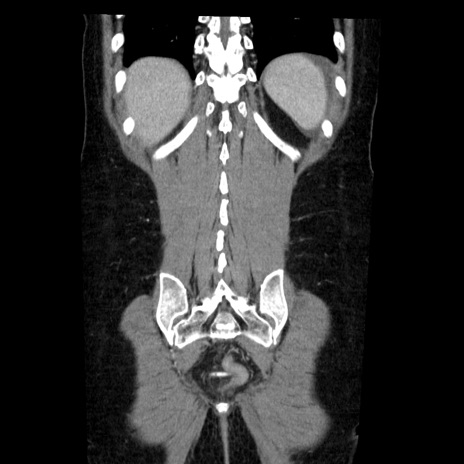

症例6(冠状断像)

【症例】50歳代女性

【主訴】下腹部痛

【現病歴】本日朝より下痢2回あり。 昼食を食べた後、嘔吐3回、下腹部痛認め、症状軽快せず、当院救急搬送。

最終食事:本日昼(生ものなし)。 昨日の夜、刺身を食ぺたとのこと。周囲に同様の症状の者なし。普段、排便は毎日あるとのこと。

【既往歴】卵巣癌術後(8年前に当院で卵巣摘出)

【身体所見】 意識清明、腹部:平坦、腸蠕動音→、やや硬、下腹部自発痛・圧痛あり、反跳痛あり、筋性防御なし。

【データ】WBC 16000、CRP 0.01